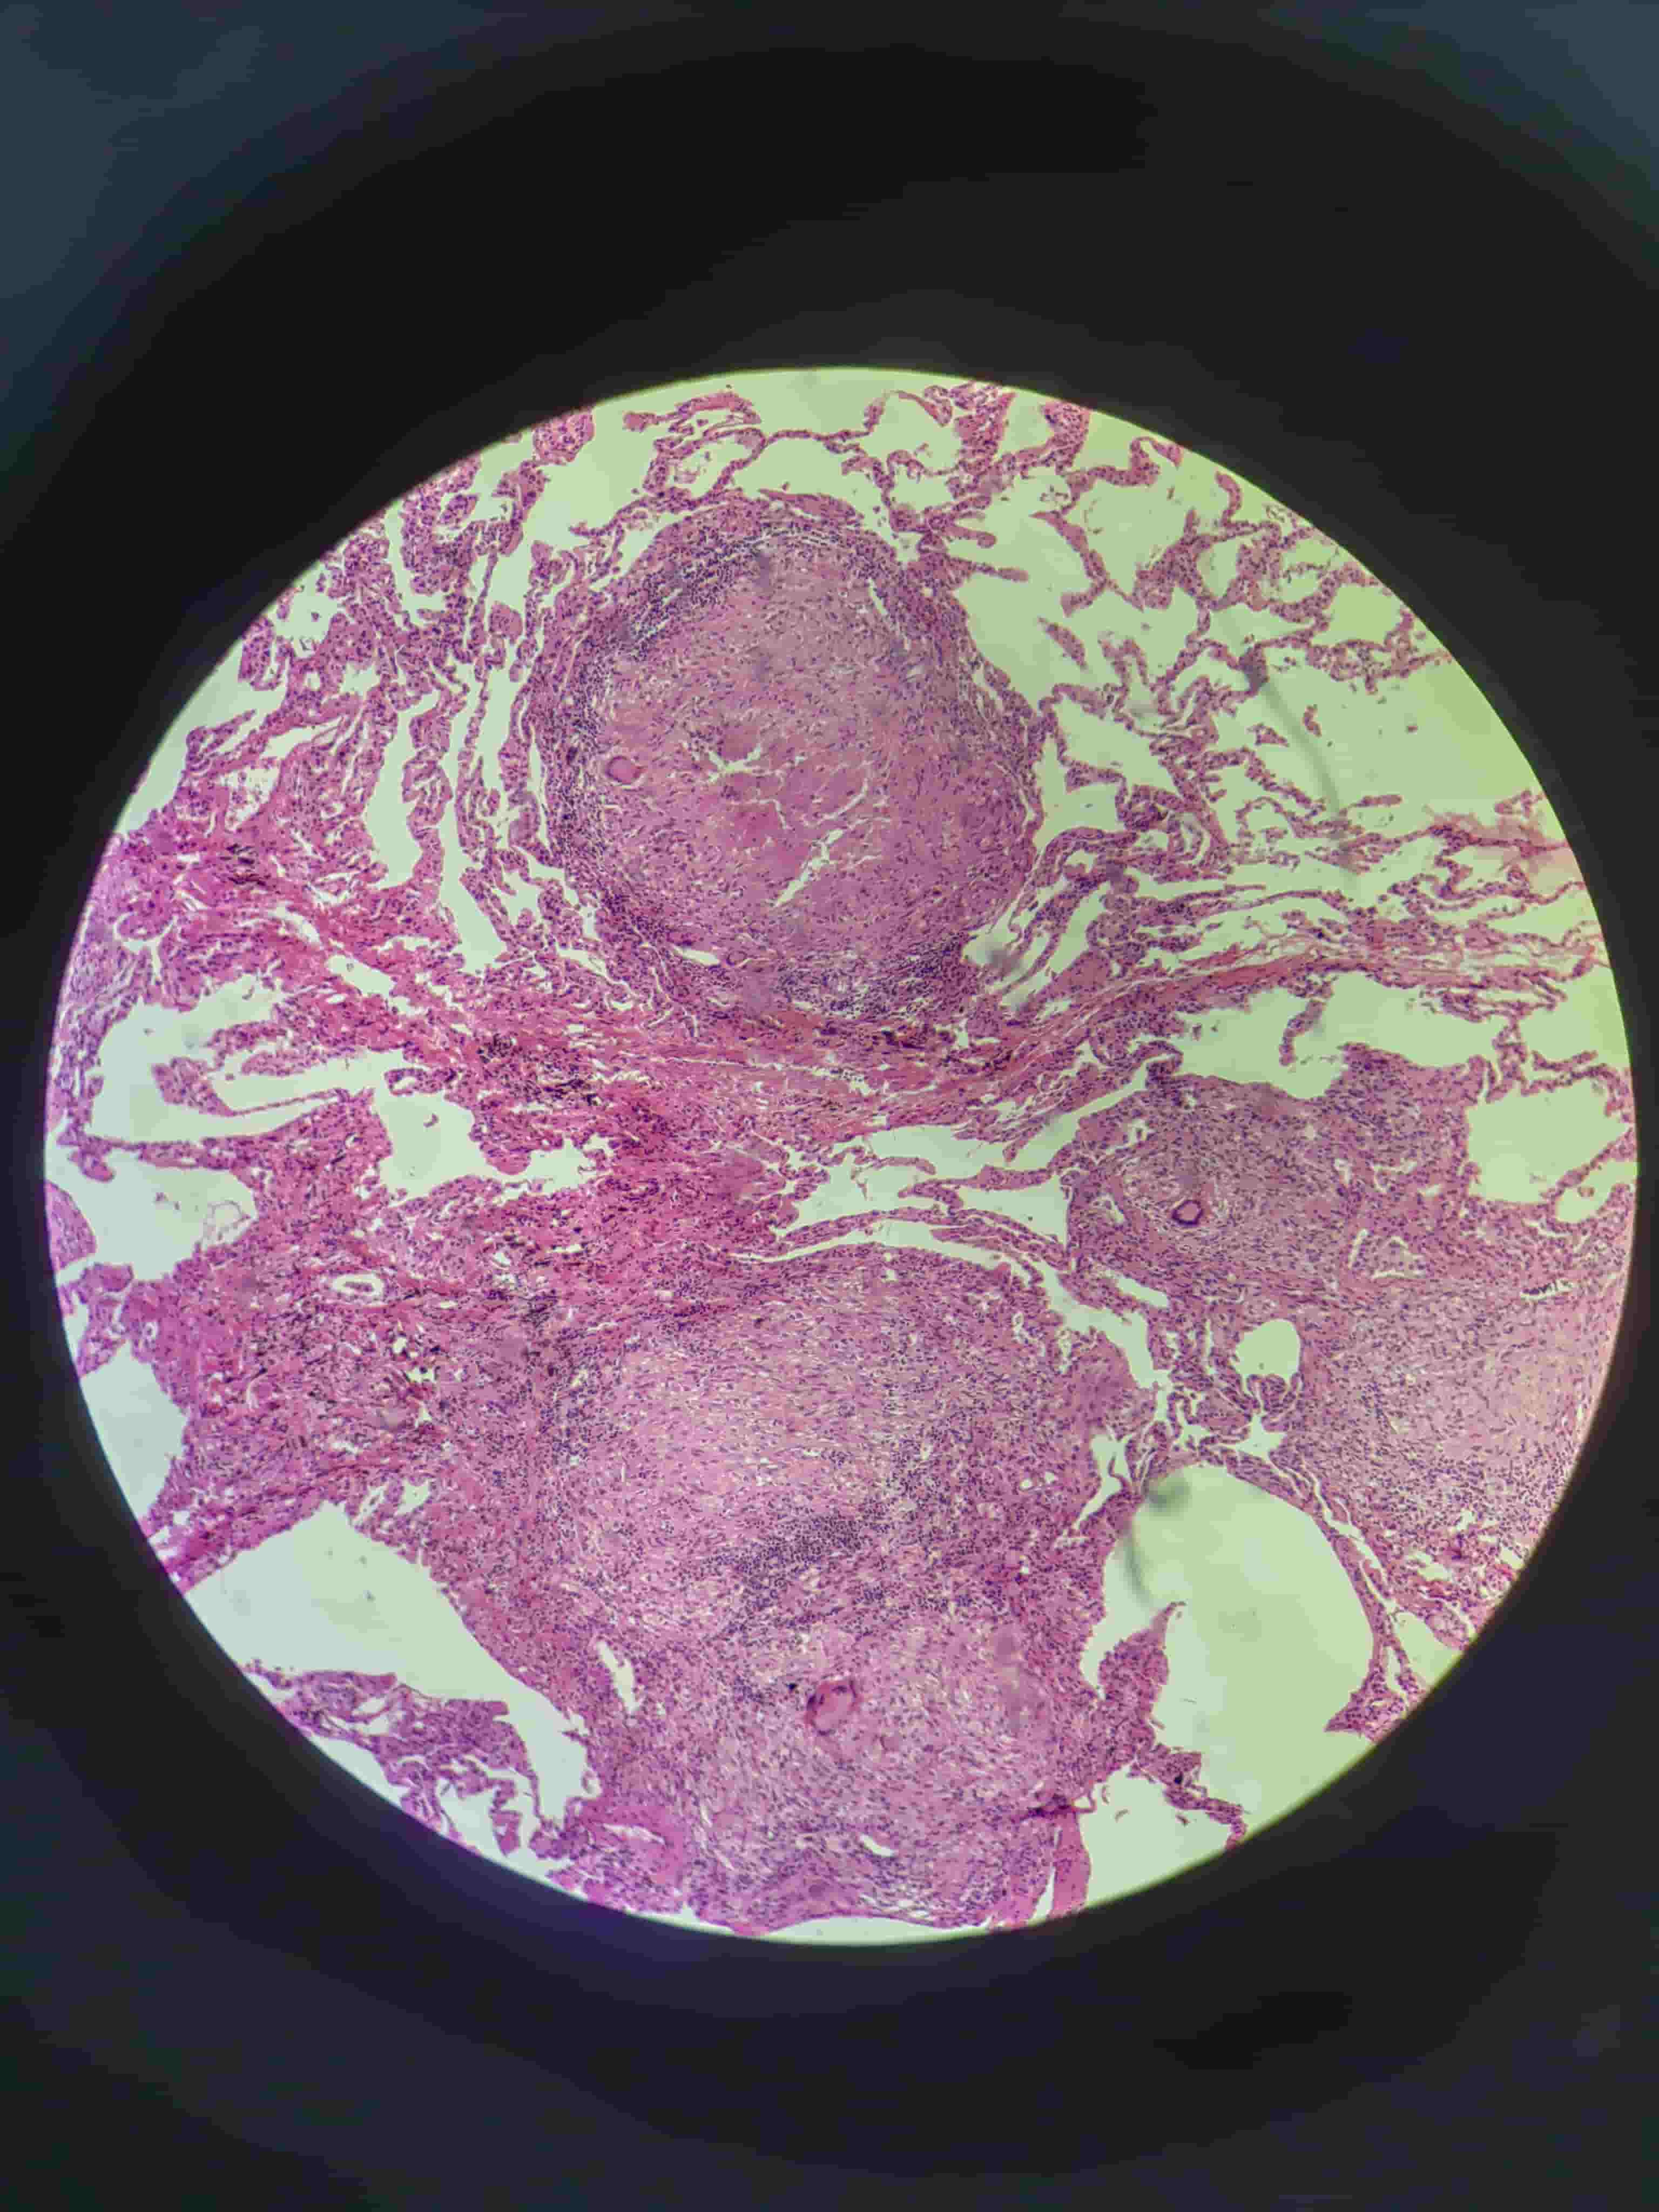

硅肺.0.0

硅肺.0.1

硅肺.0

硅肺.1

硅肺.2

硅肺